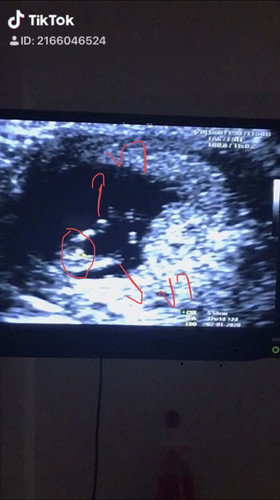

เพศลูก

พอดีเราเพิ่ง 12 w ไปอัลตร้าซาวดูการเจริญเติบโต หมอแอบให้ดูห่างขา หมอบอกมีลุ้น ผช เพราะมีติ่ง ... ใครมีประสบการณ์บ้างคะ ดูให้แม่หน่อย คาดเดา ลุ้นกันไปเนาะ

น่าจะ ช.ค่ะ